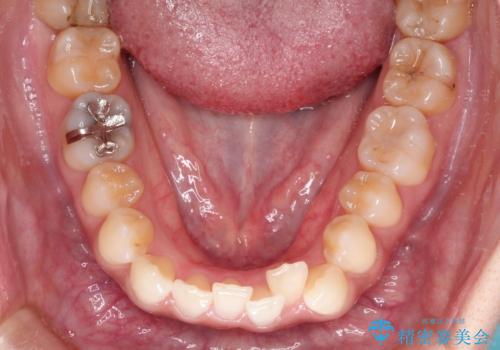

前歯のがたつきと反対咬合 インビザラインによる矯正治療

- 前歯のがたつきと反対咬合を主訴に来院されました。

下の前歯のがたつきを改善するために、右下の奥歯を後方に移動させるのと、歯と歯の間をわずかに削り、歯を並べる計画としました。

前歯の正中のずれを修正するのに少し時間がかかりましたが、整った歯並びにすることができました。